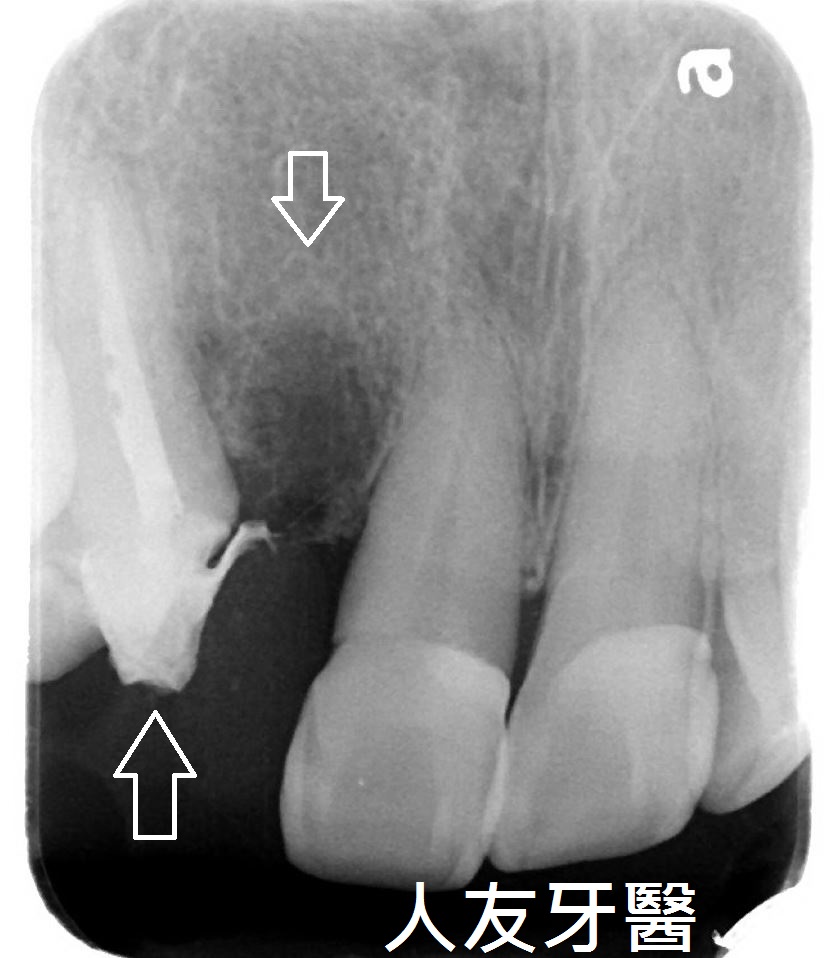

3.拔牙與骨釘:為騰出空間進行矯正,需要拔牙;骨釘用於輔助移動牙齒,初期可能會有異物感,但通常很快能適應。(下兩圖)

拔牙後放骨釘關閉空間原理與優點:

1.骨釘是植入在骨頭中的支撐點,提供穩定的錨定力量,確保牙齒移動的方向不受影響。

2.傳統矯正中移動牙齒可能造成其他牙齒跟著移動,使用骨釘可以精準控制牙齒的移動方向,讓拔牙後的縫隙能有效且正確地關閉。

3.骨釘可以大幅提升牙齒移動的效率,可能縮短矯正療程時間。

4.除了關閉拔牙空間,骨釘還能應用於骨性暴牙、嚴重深咬等情況,讓治療範圍更廣。